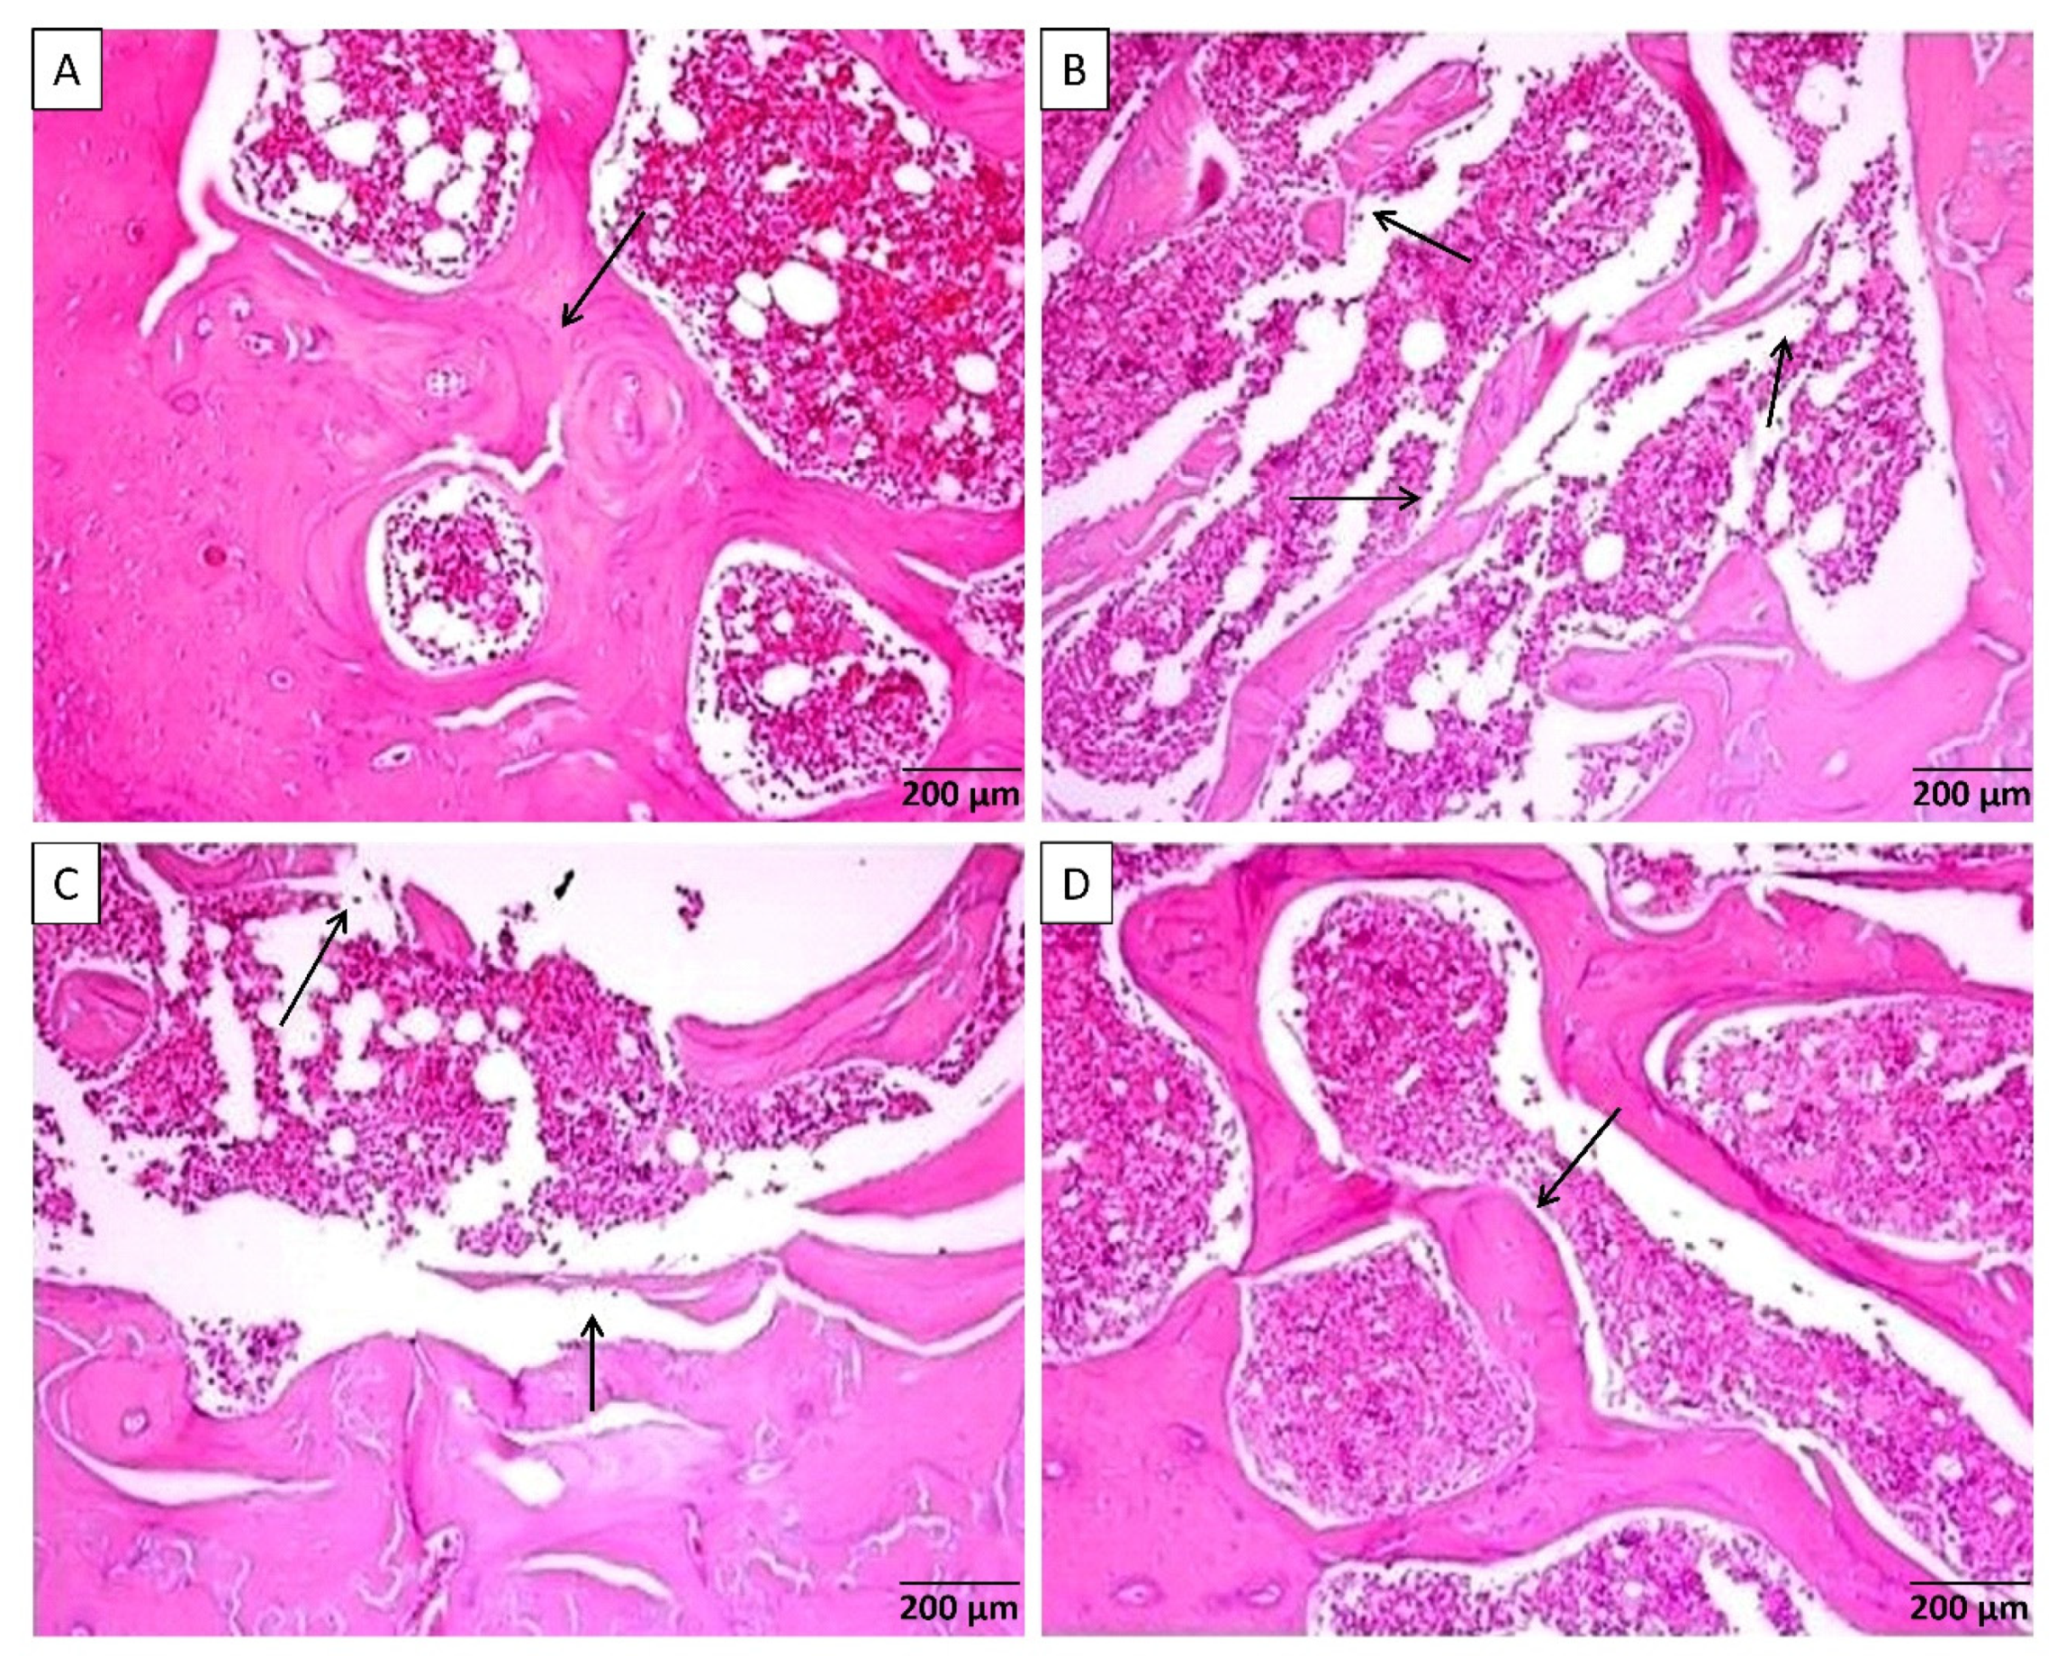

| Osteoclast surface/bone surface | Oc.S/BS | % | 1.9 ± 0.09 | 3.2 ± 0.4 **,a | 2.8 ± 0.3 | 2.1 ± 0.1 *,b | 0.0065 |

| Porosity area/cortical bone area | Po.Ar/Ct.Ar | % | 2.1 ± 0.5 | 4.2 ± 0.4 *,a | 3.4 ± 0.4 | 2.6 ± 0.4 | 0.0126 |

| Osteoid volume/cortical bone area | OV/Ct.Ar | % | 1.4 ± 0.3 | 3.6 ± 0.5 **,a | 2.9 ± 0.55 | 2 ± 0.3 | 0.0084 |

| Mineralizing surface/osteoid surface | MS/BS | % | 57.1 ± 6 | 18.9 ± 4 ***,a | 28.6 ± 5 **,a | 38.4 ± 6 | 0.0004 |

| Fibrosis tissue volume/cortical bone area | Fb.V/Ct.Ar | % | 0.02 ± 0.009 | 0.2 ± 0.04 ***,a | 0.1 ± 0.03 | 0.08 ± 0.02 *,b | 0.0015 |

| Osteoclast surface/bone surface | Oc.S/BS | (%) | 5.4 ± 2.1 | 19.2 ± 3.1 **,a | 12.4 ± 2.4 | 9.5 ± 1.6 *,b | 0.0042 |

| Trabecular thickness | Tb.Th | (µm) | 69.4 ± 3 | 30.4 ± 6 ***,a | 43.5 ± 5 **,a | 51.2 ± 4 *,b | <0.0001 |

| Trabecular number | Tb.N | (mm) | 3.5 ± 0.14 | 2.5 ± 0.2 **,a | 2.9 ± 0.12 | 3.2 ± 0.2 *,b | 0.0032 |

| Osteoid volume/bone volume | OV/BV | (%) | 8.3 ± 1.6 | 37.4 ± 6.3 ***,a | 28.5 ± 5.5 *,a | 21.2 ± 2.9 | 0.0015 |

| Mineralizing surface/osteoid surface | MS/BS | (%) | 37.4 ± 4.3 | 17.4 ± 3.1 **,a | 27.3 ± 4.2 | 32.2 ± 3.5 | 0.0095 |

| Fibrosis tissue volume/tissue volume | Fb.V/TV | (%) | 0.1 ± 0.003 | 0.35 ± 0.07 **,a | 0.2 ± 0.04 | 0.12 ± 0.05 *,b | 0.0054 |